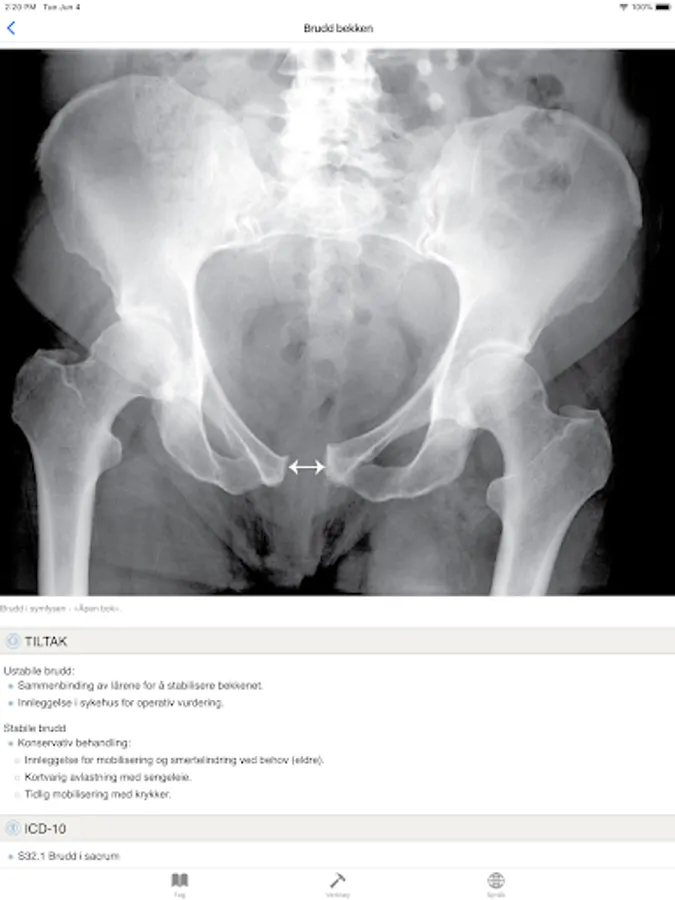

Pelvic Fracture